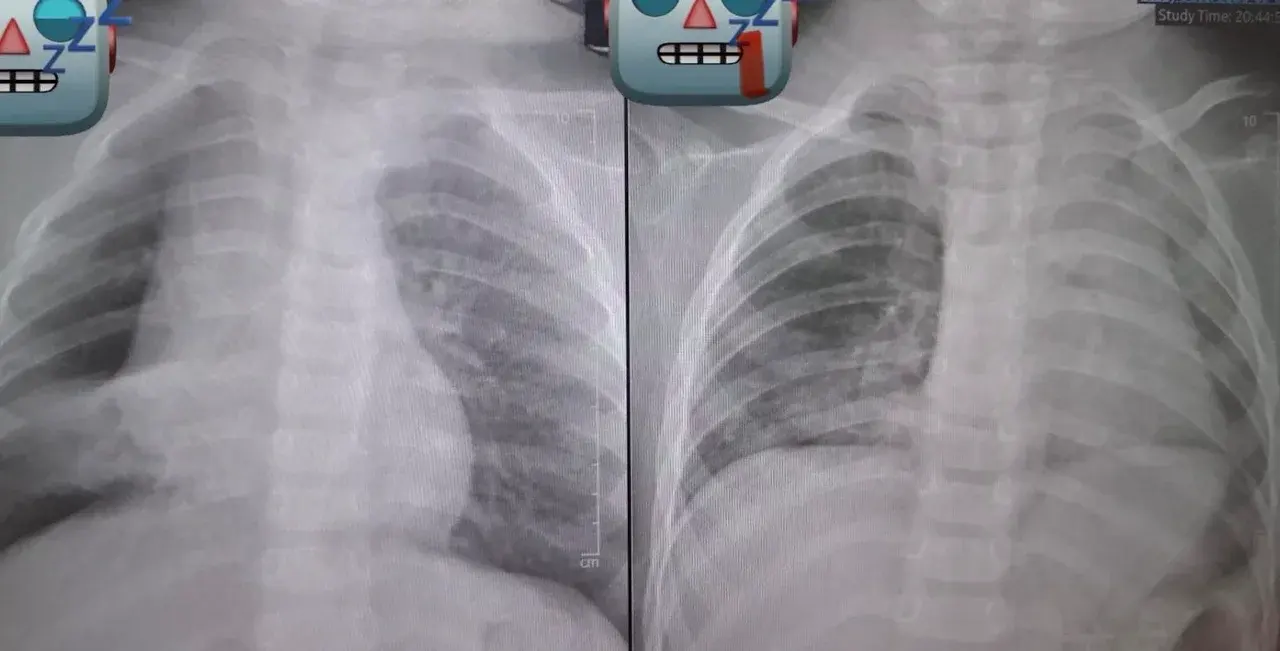

เหตุการณ์นี้เกิดขึ้นเมื่อคุณย่าป้อน ถั่วลิสงแบบเต็มเมล็ด ให้หลานวัย 1 ขวบทาน หลังจากนั้นเพียง 3-4 วัน เด็กเริ่มมีอาการผิดปกติ คือ ไอเรื้อรังและมีเสียงหายใจหวีด เมื่อนำตัวส่งโรงพยาบาล ผลเอกซเรย์พบว่าถั่วลิสงหลุดเข้าไปอุดกั้นในหลอดลม จนทำให้ลมไม่สามารถเข้าสู่ปอดได้ ส่งผลให้ปอดบางส่วนยุบตัวลง

ความยากในการรักษา: เนื่องจากสิ่งแปลกปลอมติดค้างอยู่นานหลายวัน ร่างกายจึงสร้างเนื้อเยื่ออักเสบขึ้นมาหุ้มถั่วไว้ ทำให้ถั่วมีลักษณะลื่นและขยับไปมาในหลอดลม (Dancing Peanut) ทีมแพทย์ต้องใช้ความชำนาญอย่างสูงในการส่องกล้องคีบออกมาเพื่อช่วยชีวิตเด็ก